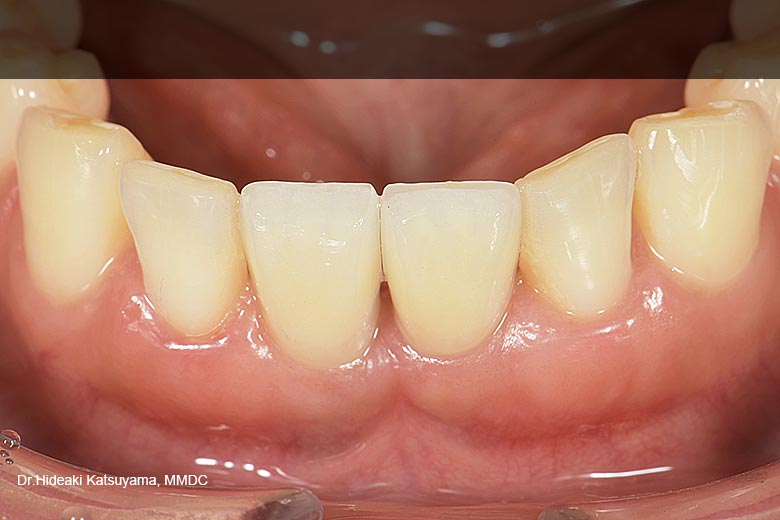

スクリュー固定式の最終的な上部構造が装着された状態です。 スクリュー固定式の最終的な上部構造が装着された状態です。

-

上部構造は、チタンベース(土台)にジルコニアクラウンを接着した構造となっています。単一のクラウンで修復を行いました。 上部構造は、チタンベース(土台)にジルコニアクラウンを接着した構造となっています。単一のクラウンで修復を行いました。

審美的な結果が得られ非常に結果に満足いただけました。 審美的な結果が得られ非常に結果に満足いただけました。